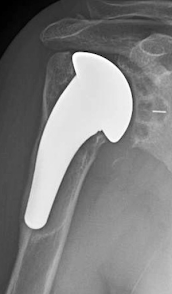

As shown in Short stem humeral components in reverse shoulder arthroplasty: stem alignment influences the neck-shaft angle this inconstant anatomy can result in variable positioning of a short stemmed component in the canal.

This can result in variable positioning of the proximal aspect of the component as well as point loading of the diaphysial canal (red arrows).

It appears that without the stabilizing effect of a standard length stem, loading of a short stemmed component can cause it to collapse into varus.